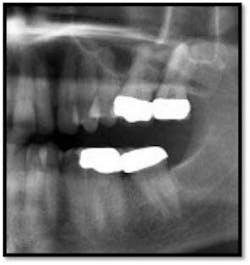

TX FM Perioscopy with local anesthetic FM LANAP Surgical Procedure •bone sounding was performed on all teeth included in this procedure •occlusal adjustment performed resulting in reduction in centric prematurities •Orthodontic referral for anterior spacing •3 month periodontal maintenance14 months post TreatmentPocket reductions of up to 4mm

The patient now has a stable dentition and has moved forward with Invisalign orthodontia to correct the overbite and spacing in her anterior teeth.

The posterior crowns still present a challenge to keep clean and will be scheduled for replacement post orthodontic treatment.